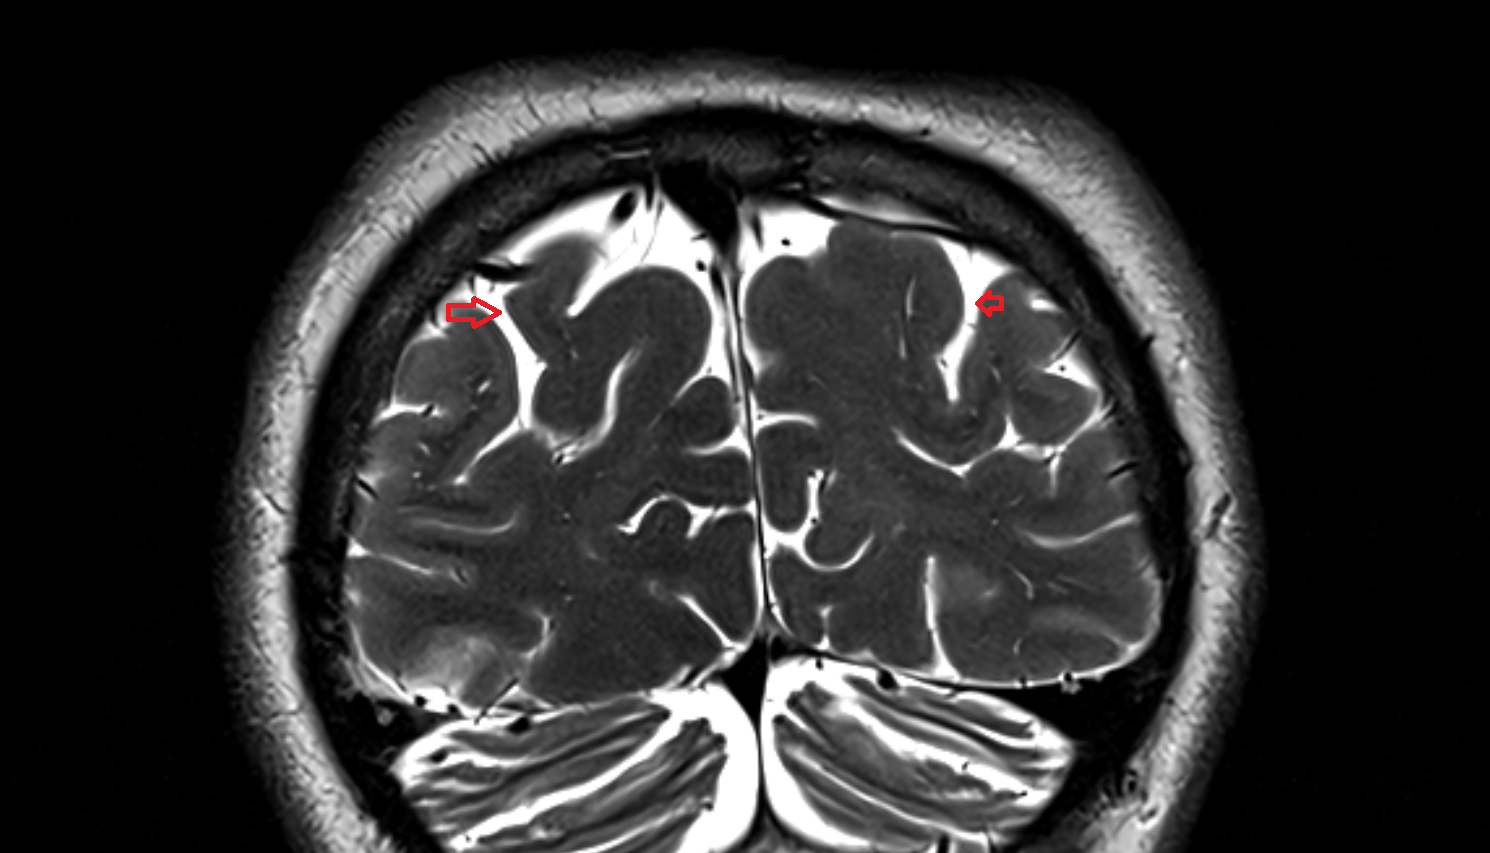

- Fetal brain

- Fetal caudate nucleus

- Fetal thalamus

- Fetal cerebellum

- Fetal occipital lobe

- Fetal temporal lobe

- Fetal parietal lobe

- Fetal frontal lobe

- Fetal third ventricle

- Fetal lateral ventricle